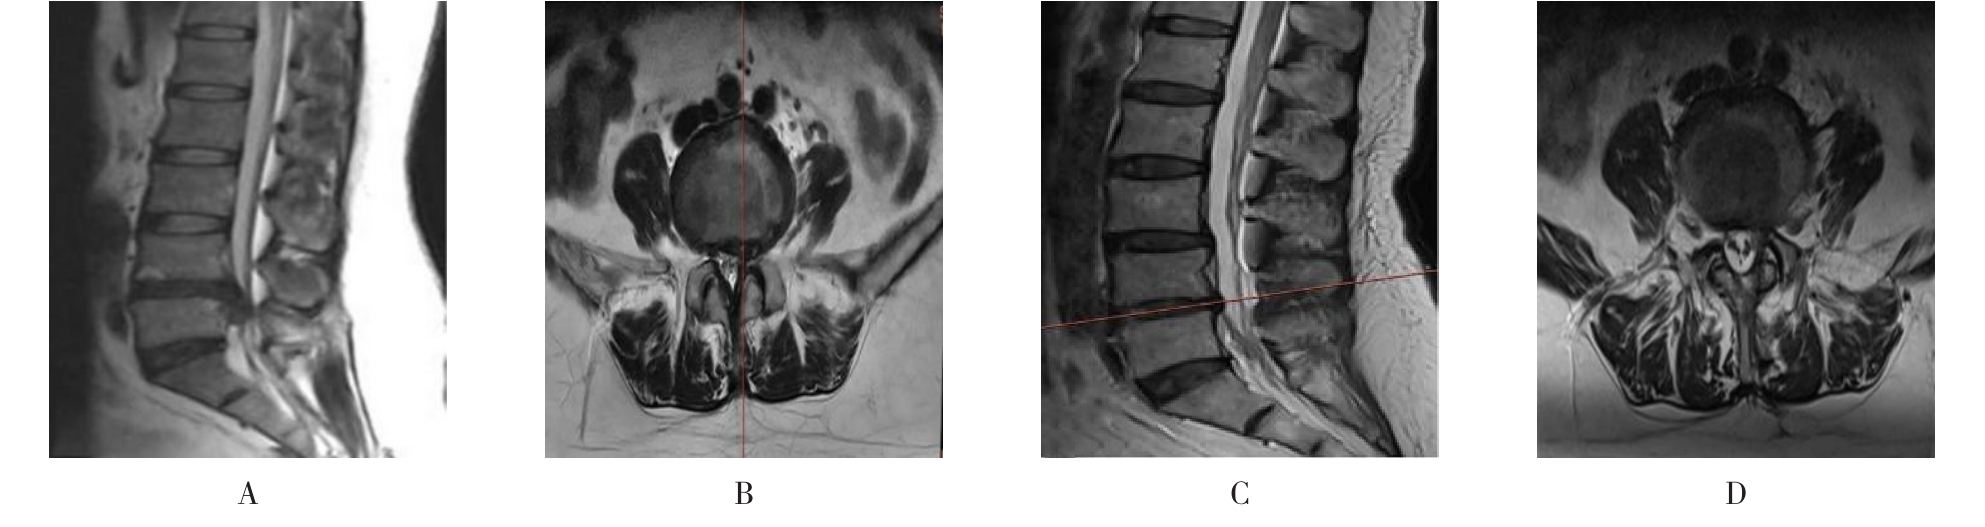

• 不同入路脊柱内镜手术治疗L4/5节段脱垂型腰椎间盘突出症的疗效比较

摘要:目的 观察经椎间孔入路内镜下腰椎间盘切除术(TELD)和经椎板间入路内镜下腰椎间盘摘除术(IELD)治疗L4/5节段脱垂型腰椎间盘突出症(LDH)的临床疗效。方法 回顾性分析2020年11月-2022年11月该院采用脊柱内镜手术治疗的75例L4/5节段脱垂型LDH患者的临床资料。根据手术入路的不同,将患者分为TELD组(53例)和IELD组(22例)。比较两组患者的手术情况和术后疗效。结果 与TELD组比较,IELD组的手术时间明显缩短,术中透视次数明显减少,差异均有统计学意义(P < 0.05);两组患者住院时间和并发症发生率比较,差异均无统计学意义(P > 0.05)。所有患者术后均获得12~19个月的随访。两组患者末次随访时的视觉模拟评分法(VAS)评分和Oswestry功能障碍指数(ODI)明显低于术前,且IELD组明显低于TELD组,差异均有统计学意义(P < 0.05)。按照突出物和神经根的不同位置进一步分析,两组肩上型患者(TELD组10例,IELD组6例)末次随访时的VAS评分和ODI明显低于术前,且IELD组末次随访时的VAS评分明显低于TELD组,差异均有统计学意义(P < 0.05);两组腋下型患者(TELD组8例,IELD组16例)末次随访时的VAS评分和ODI明显低于术前,且IELD组明显低于TELD组,差异均有统计学意义(P < 0.05);35例肩前型患者经TELD术后,末次随访时的VAS评分和ODI明显低于术前,差异有统计学意义(P < 0.05)。按照突出物的不同Lee分区进一步分析,两组Lee Ⅲ区患者(TELD组44例,IELD组10例)末次随访时的VAS评分和ODI明显低于术前,且IELD组的ODI明显低于TELD组,差异均有统计学意义(P < 0.05);两组Lee Ⅳ区患者(TELD组9例,IELD组12例)末次随访时的VAS评分和ODI明显低于术前,且IELD组明显低于TELD组,差异均有统计学意义(P < 0.05)。结论 采用TELD和IELD治疗L4/5节段脱垂型LDH,均可获得较满意的减压效果,但IELD的手术时间相对较短,X线透视次数较少,且对肩上型、腋下型、Lee Ⅲ区和Lee Ⅳ区的减压效果更有优势。